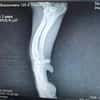

Licas ist ca. 11/24 geboren, etwa 30 cm groß und wiegt ungefähr 7 kg. Er wurde gemeinsam mit seiner Mama verlassen auf einem Feld in Rumänien gefunden. Eine Tierschützerin hat die zwei aufgenommen das war bereits im Oktober letzten Jahres. Doch Licas brachte ein schweres Schicksal mit: Sein Vorderbein ist gelähmt. Nach dem Röntgen stand fest eine Amputation oder eine Prothese könnten ihm helfen, schmerzfrei und unbeschwert durchs Leben zu gehen.